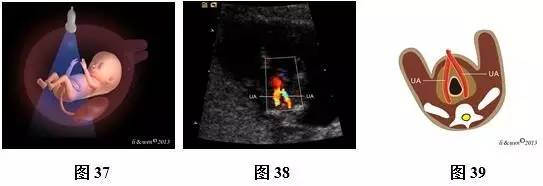

(三)11~13+6孕周胎儿腹部扫查方法及观察内容

超声扫查方法:声束通过胎儿上腹部的胃泡、肝脏横断扫查(图31),可获得上腹部横切面图(图32,33),然后声束平面向胎儿尾侧平移扫查,通过脐带腹壁插入口时(图34),可获得脐带腹壁插入口横切面(图35,36)。通过膀胱时(图37),可即获得膀胱水平横切面(图38,39)。

标准切面判断标准:腹部呈圆或椭圆形,脊柱为横切面,上腹部横切面可见正常胃泡位于左侧,肝脏位于右侧;脐带腹壁插入口横切面可见脐带腹壁入口位于前腹壁中央,与后腹壁脊柱回声连成一直线构成此平面的前后中轴线;膀胱水平横切面彩色多普勒可见膀胱位于盆腔内,呈无回声,在膀胱的两侧各有1根脐动脉,略向脐孔处旋转探头,可见脐血管在腹正中处进入脐带内。

主要观察的内容:(1)上腹部横切面:主要观察内容是胃泡及肝脏位置、大小。正常胃泡位于腹腔左侧,肝脏位于腹腔右侧。(2)脐带腹壁插入口横切面:腹壁完整性与连续性,脐带腹壁入口处位置是否正常、有无包或肠管外翻等。(3)膀胱水平横切面彩色多普勒:观察脐动脉数目,膀胱位置、大小及壁的厚度等。

注:ST为胃泡;LIVER为肝脏;SP为脊柱;IVC为下腔静脉;AO为腹主动脉;UA为脐动脉;L为左侧;R为右侧;

图31~39 11~13+6孕周胎儿腹部扫查方法、声像图及模式图。图31上腹部横切面图扫查模式图;图32、33上腹部横切面图声像图及模式图;图34脐带腹壁插入口横切面扫查模式图;图35、36脐带腹壁插入口横切面声像图及模式图(黑色箭头示脐带腹壁入口);图37膀胱水平横切面扫查模式图;图38、39膀胱水平横切面彩色多普勒。